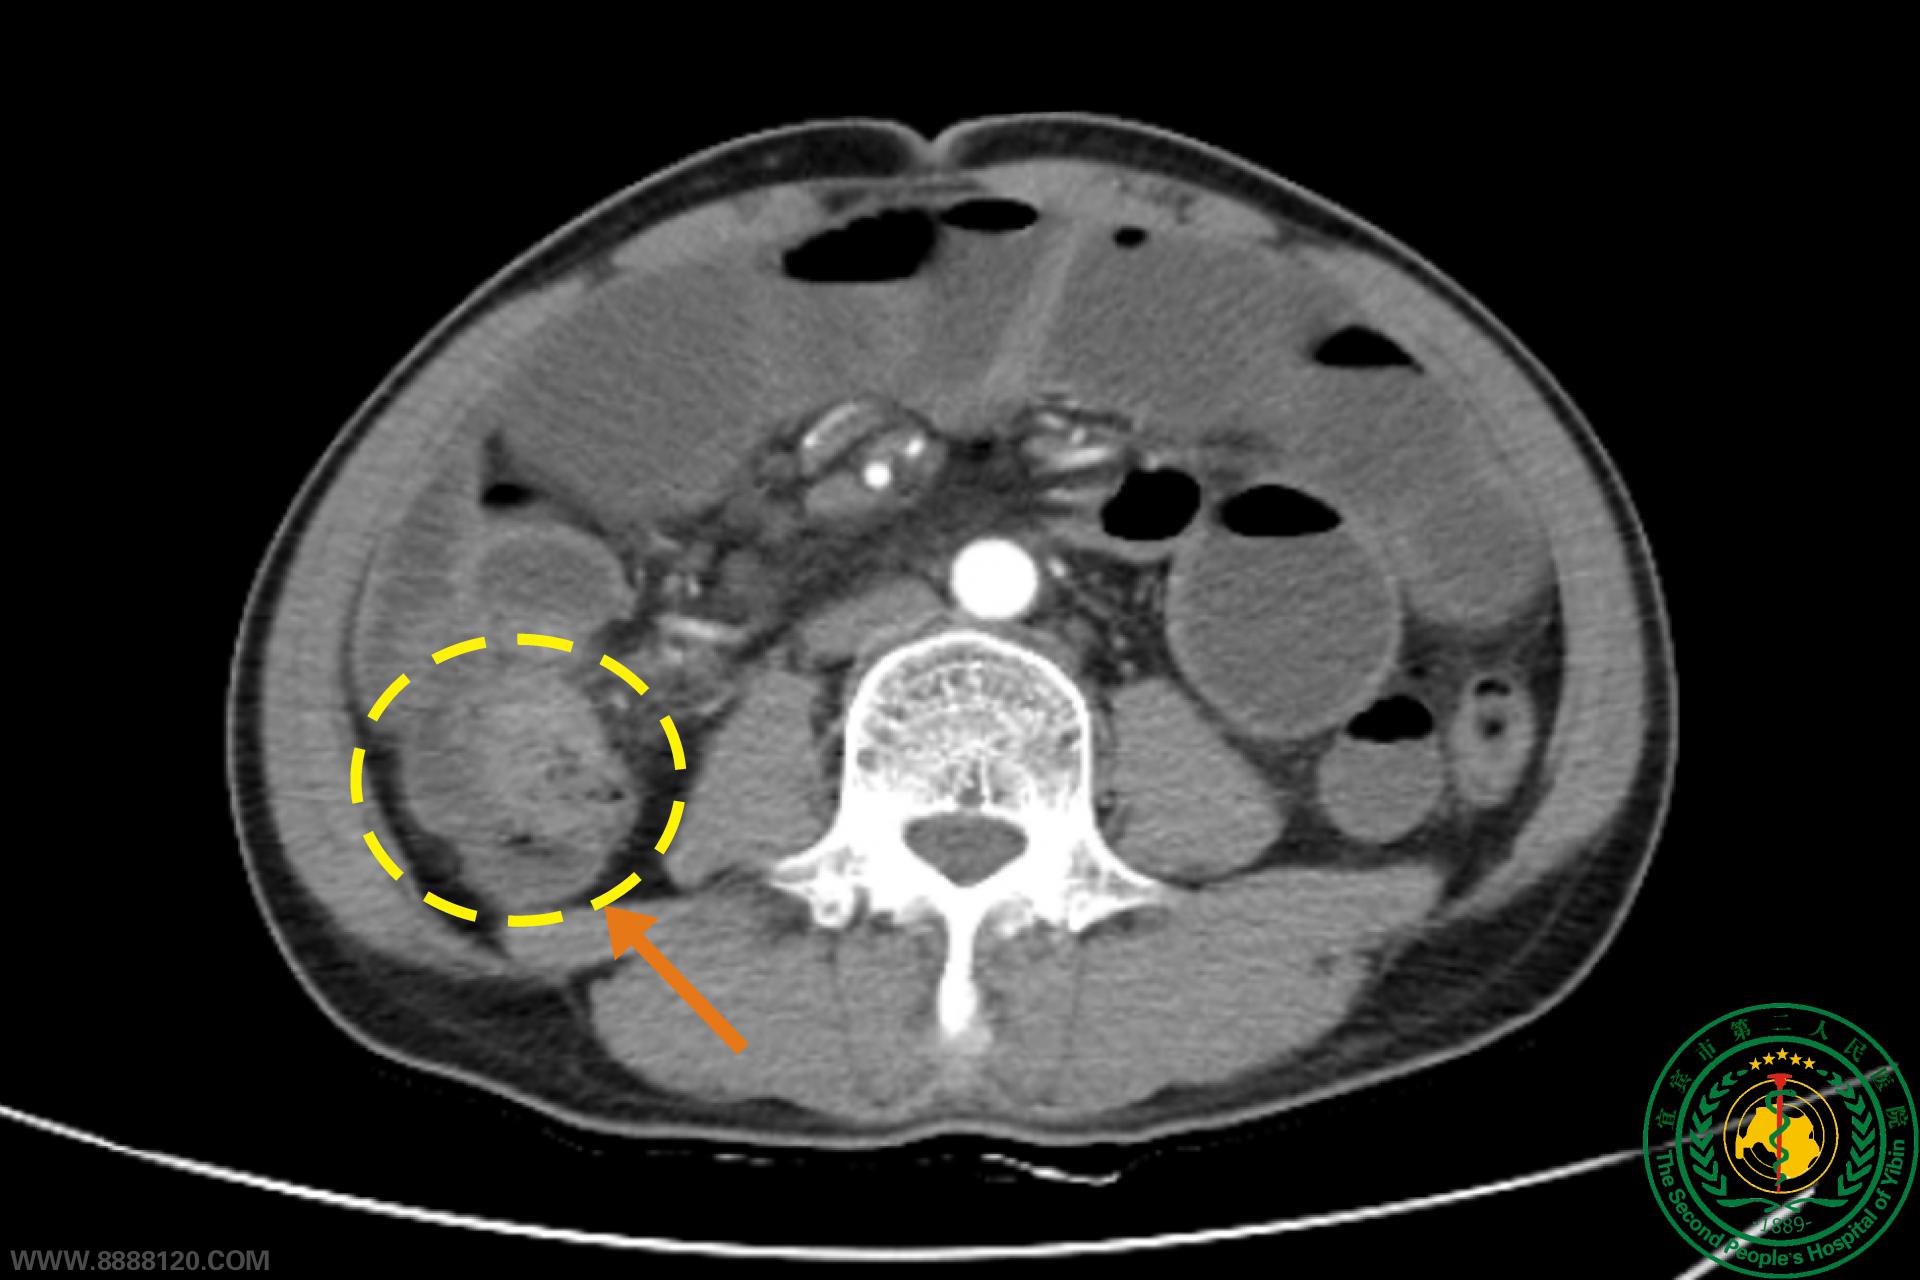

梗阻性结肠癌也可以做腹部无切口根治性手术

梗阻性结肠癌也可以做腹部无切口根治性手术54054